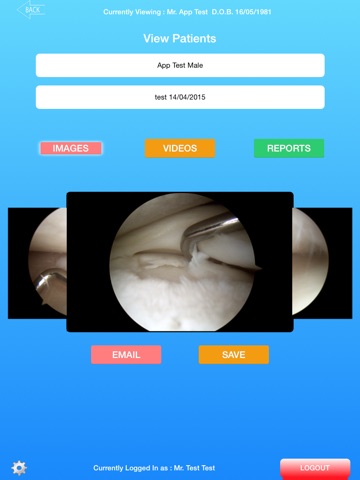

The Medic App is an app for surgeons who utilise Medicap Surgical documentation and recording system. Stream surgical images, video and reports directly to your own personal Apple device to browse or consult with your patients. Save content and take it away with you by simply saving the content to your iPad.

The Medic App is an effective tool for any surgeon or hospital staff member to transport and share content from our servers.